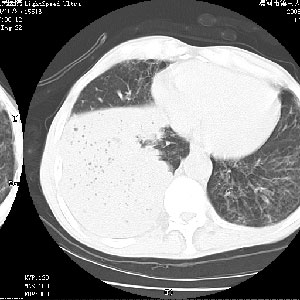

m 老年 发烧、呼吸困难,慢支、肺气肿多年;记的那次是下午大概17:38做的,晚上窒息死亡。

上面的层面就慢性支气管炎肺气肿、肺大泡,别的没有什么、也就不传了。

当时我怀疑:1、阻塞性肺不张早期 2、肺脓肿早期,望老师们发表意见

应该是脓胸的表现,右下肺气管阻塞考虑为痰栓.

你怀疑的有道理,慢支、肺气肿、肺打泡是有了,右下肺的病变有待商议;

首先考虑右下肺炎症并不张,不除外早期肺泡癌改变

病灶边缘清---多个含气小腔---近端未见通畅气管影-----支持-----慢性肺脓肿继发阻塞性肺不张

阻塞性肺不张原因-----脓液未排出

1、右侧脓胸;2、copd;

3、细支气管肺泡癌可以排除,病变以斜裂为界,呈大片状高密度影,内可见多发小气泡,表明有产气杆菌感染所致,内无明显的支气管“枯树枝征”表现,再结合其临床改变(细支气管肺泡癌临表表现重、影像表现轻)所以不符合细支气管肺泡癌(炎症型)的改变。